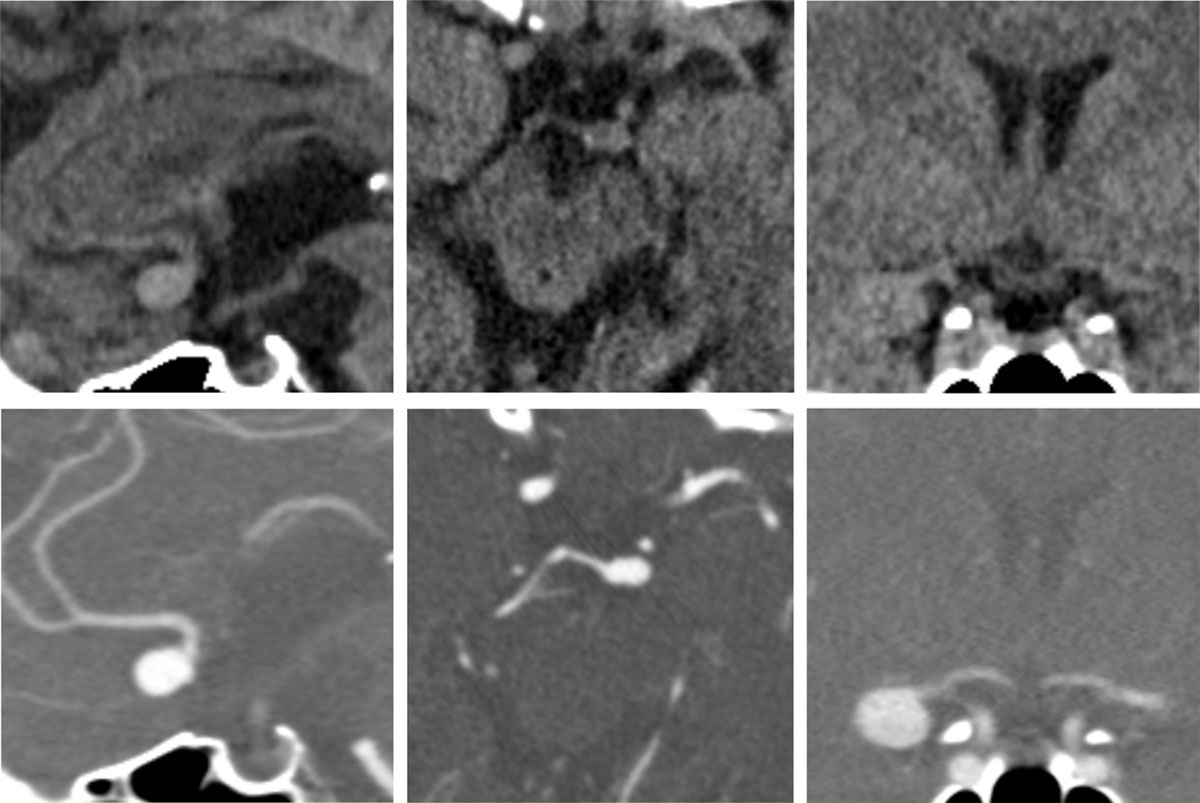

Examples of reconstructed images from the NECT datasets (upper row) and corresponding images from CT angiographies (lower row). Left: sagittal reconstruction of an aneurysm of the anterior communicating artery. Middle: axial reconstruction of an aneurysm of the basilar tip. Right: coronar reconstruction of an aneurysm of the middle cerebral artery.